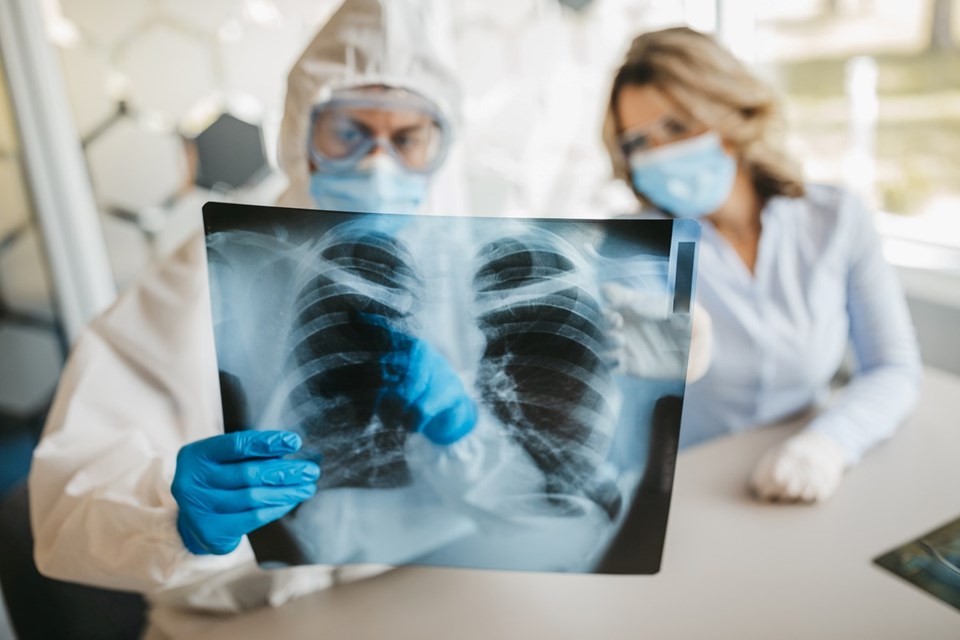

AKCİĞER HÜCRELERİNE ULAŞMADA BAŞARILI

Çalışmada, corona virüsün önceki varyantlarındaki spike proteini ile karşılaştırıldığında, Delta varyantının akciğer hücrelerine ulaşmada daha başarılı olduğu ve virüs bulaşan hücreleri bir araya getirebildiği açıklandı.